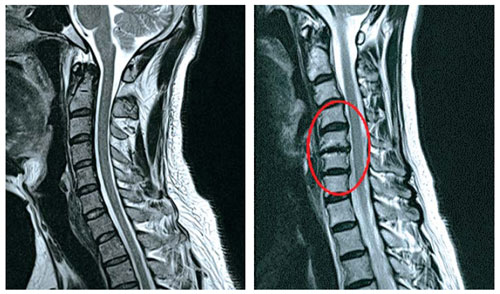

목 디스크는 목의 디스크(경추 디스크)에서 출현하는 질환으로, 경추 디스크 사이의 연골판이 터져 디스크 내부 물질이 경추 신경을 자극해 통증이나 저림증 등의 증상을 유발 해요. 목 디스크는 일상생활에서의 안 좋은 자세나 많은 운동, 부상 등이 이유가 되는 것이 될 수 있기도하고, 시간이 지날수록 발생 확률이 높아져요. 목 디스크의 증상으로는 목 부위의 통증, 팔의 저림, 근육 약화 등이 있으며, 증상이 난폭한 경우 수술 등의 치료가 필요할 수 있어요. 그리하나 대개의 경우 치료 없이도 시간이 지나면 증상이 호전되는 경우가 대부분입니다.

목디스크 증상 목 자세이고요. 현대인들은 스마트폰이나 모니터를 많이 사용하다보니 목이 앞쪽으로 당겨져있는 것처럼 자세를 많이 취하게 된다 하였습니다. 이런 자세는 정상적인 목뼈를 전환 시켜 여러분이 아시는 거묵목 증상이 나타나게 되는 이유가 되는 것입니다.

추간판의 수핵이 빠지거나 퇴행성 경추증 및 경추관협착증 등으로 척수가 압박되면 대다수 팔에 힘이 빠지는 것을 느끼게 돼요. 척수가 눌리는 정도이기 때문에 한쪽 팔만 마비될 수 있고요. 하지마는 양팔의 감각이 둔해지고 눈을 감고도 어지럽기 때문에 이러한 목 디스크 증상이 나타나면 무척 위험한 상태가 되기 때문에 빨리 치료가 필요해요.

목디스크 증상 2번째는 다리에 힘이 빠지거나 걷기 곤란한 보행장애가 보여집니다니다. 목디스크 증상은 거의 퇴행성 질환으로 40대부터 조금씩 증상이 생기는 경우가 많이 들어있습니다 이는 그릇된 생활습관이나 오랜시간 앉아있을 때 디스크를 비집고 나온 수핵이 척수를 압박해 신경을 누르게 되어 통증을 느끼게 된다 하였습니다. 증상의 순서의 경우 손에 힘이 빠지고 저리다가, 다리까지 힘이 빠져 걷기 쉽지 않은 보행장애가 생겨나게 된다고 합니다.